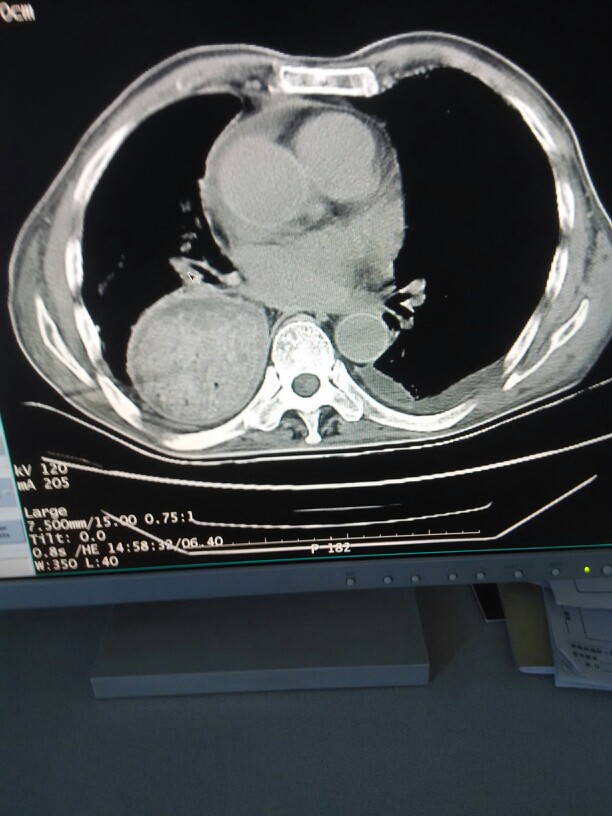

体检:T 36.7℃,P 76次/分,R 18次/分,BP 160/100mmHg。一般状况较好,体型肥胖。心肺无异常。肝脾肋下未触及。神经系统检查无异常。